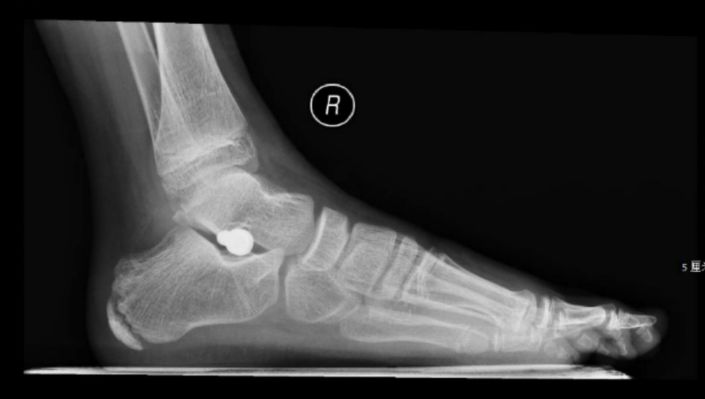

给涛涛拍片后,证实了小孩双足骨骼角度异常,涛涛的脚痛可能是平足症引起。

深圳市儿童医院骨二科韩镜明主任市内率先开展儿童经跗骨窦HyProCure螺钉置入距下关节制动术,可有效复位并稳定距骨,维持足弓,与传统手术相比,有简单安全、创伤小、手术时间短、效果确切等优点。

HyProCure螺钉是新一代的距下关节稳定器,通过在足外侧一个长约1.5-2.0cm的小切口,置入跗骨窦内,改善后足外翻及前足外展,抬高足内侧纵弓,创伤小,不需要再次手术取出。